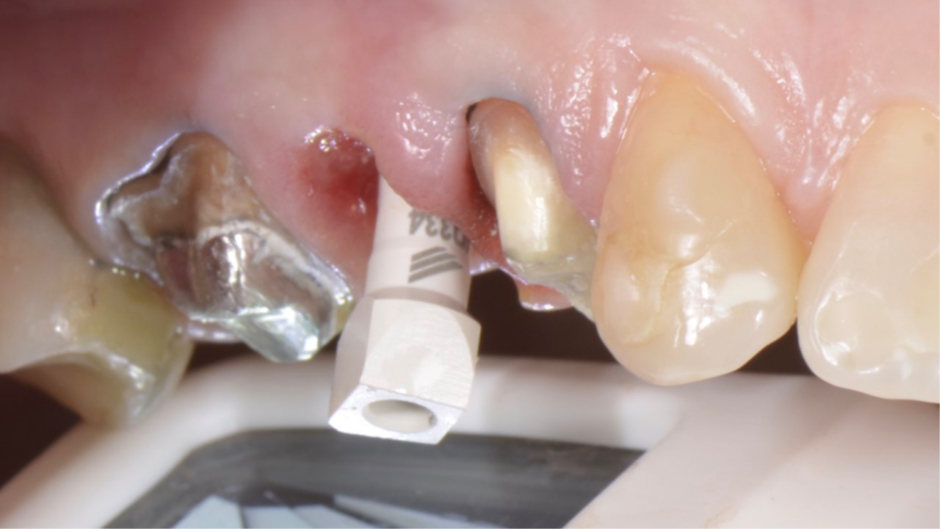

Para fazermos a coroa definitiva, precisamos posicionar a margem gengival semelhante aos dentes adjacentes. Nesse caso, usamos o túnel check de prótese CM para escolha da cinta do pilar (Figura 7). Temos que tomar muito cuidado em saber onde posicionar a margem gengival vestibular da coroa sobre implante, pois quando temos muita espessura de mucosa, a marcação do túnel check pode “confundir” no momento da seleção da cinta do pilar (Figura 8). O pilar de escolha para esse caso foi o Ideale 3.3×4 e foi planejado para ser instalado como uma cinta de 2,5mm, a fim de que a margem da coroa sobre implante fique semelhante à margem dos dentes adjacentes. Então, o pilar Ideale reto 3.3×4 com a cinta de 2,5mm foi instalado (Figura 9) para ser usado como pilar definitivo e fazer uma coroa provisória sobre o implante. A diferença de tamanho entre o diâmetro cervical do dente natural e o encaixe do implante pode resultar em um perfil inadequado da coroa. Se o perfil for subcontornado, não haverá pressão contralateral ou suporte para a mucosa, e as partículas de alimentos podem ficar retidas.

Figura 7 – Túnel check de prótese CM para escolha da cinta do pilar com muita espessura da mucosa.

Figura 8 – Túnel check de prótese CM com as marcações.

Figura 9 – Pilar Ideale reto 3.3×4 com a cinta de 2,5mm instalado.